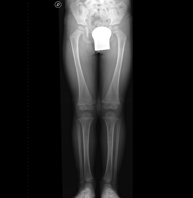

Tècnica que usa els raigs X a través de la qual s'obtenen imatges de tota la columna vertebral per al seu estudi, amb la valoració especialment de la presència d'escoliosi i dismetries pèlviques. - Telematria EEII (Extremitats Inferiors)

Tècnica que usa els raigs X a través de la qual s'obtenen imatges de la totalitat d'ambdues extremitats inferiors per al seu estudi, amb la valoració especialment de la presència de dismetries entre elles. - RX Extremitats

Tècnica que usa els raigs X a través de la qual s'obtenen imatges d'ambdues extremitats per al seu estudi. - RX Malucs